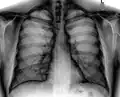

Рентгенограмма грудной клетки, демонстрирующая солитарный лёгочный узел в верхней доле левого лёгкого.